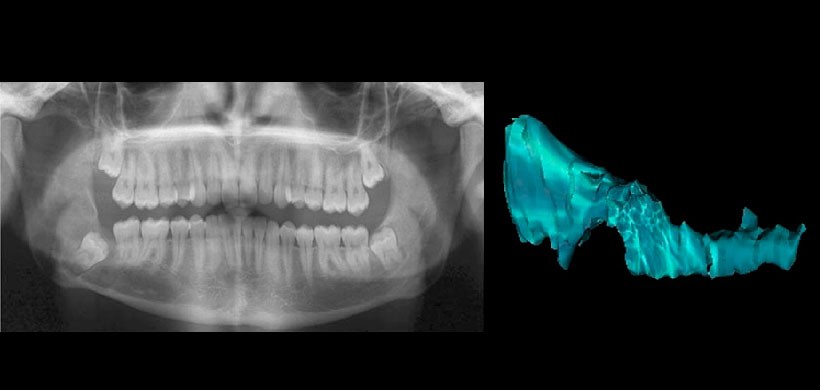

Fig 2. Radiografía panorámica y reconstrucción 3 D del volumen de la lesión, del mismo paciente con diagnóstico definitivo de tumor odontogénico queratoquístico que fue sometido a una descompresión quirúrgica hace 5 meses.